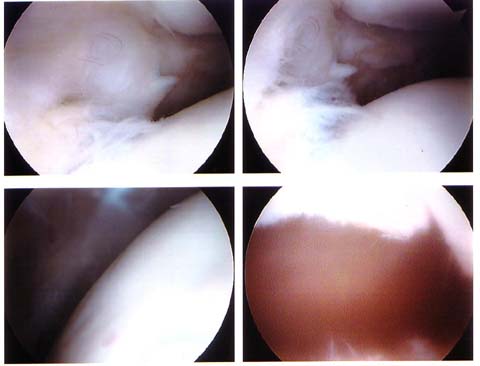

Here are the “after” pictures where everything is cleaned up.

“Smooth as a babies bottom…” Well, not quite. The resolution of this image isn’t quite there but the lower left picture does show a bit of a bumpy surface.